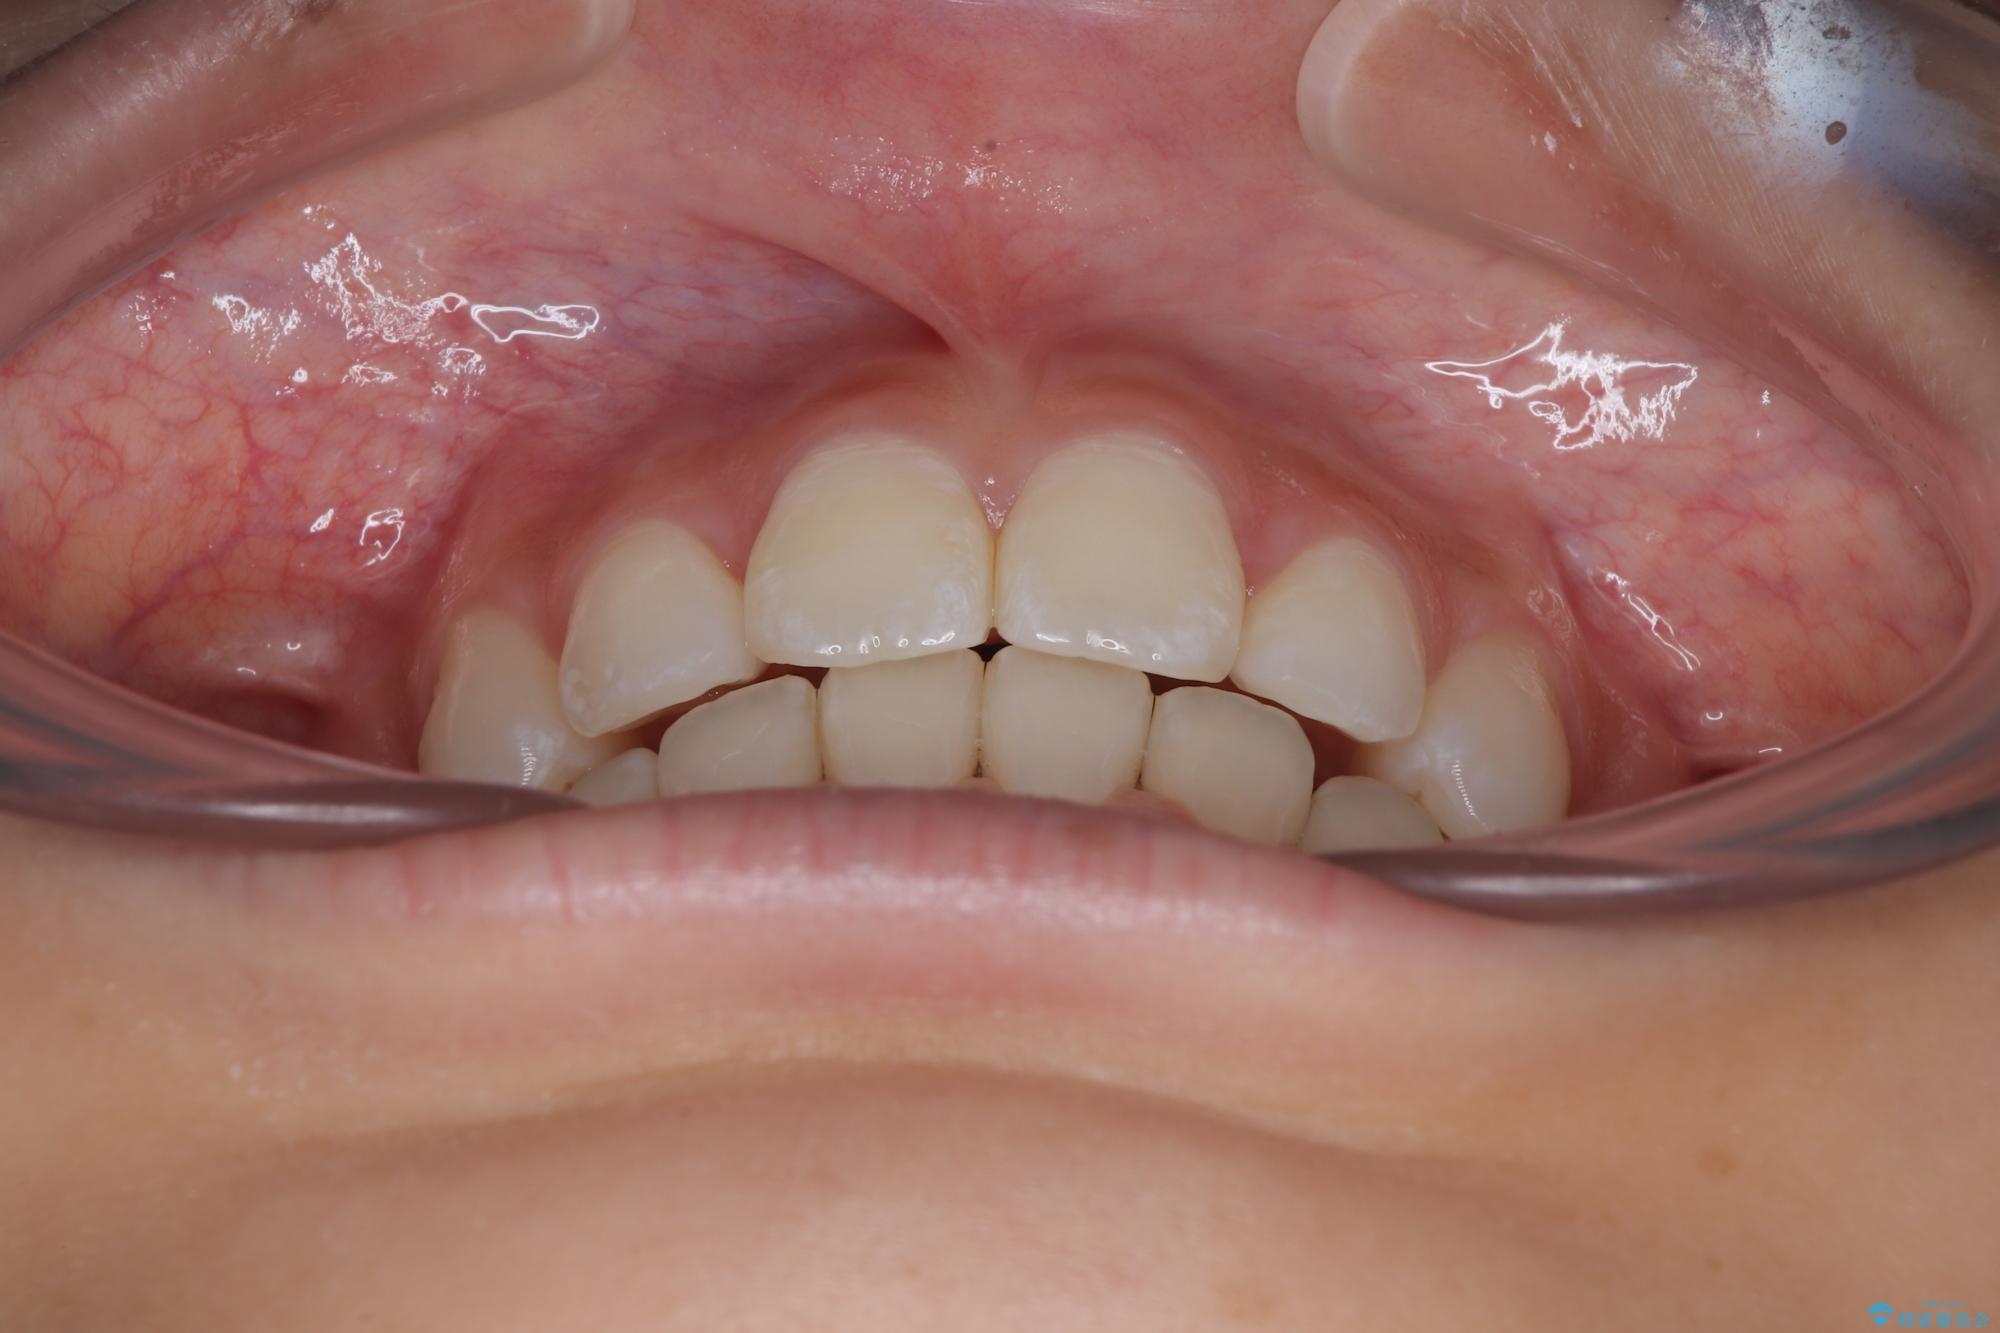

下唇に前歯が当たって跡が残ってしまう状態でしたが、スッキリとした口元に仕上げることができました。

斜め前に飛び出した前歯 抜歯矯正で素敵な横顔に